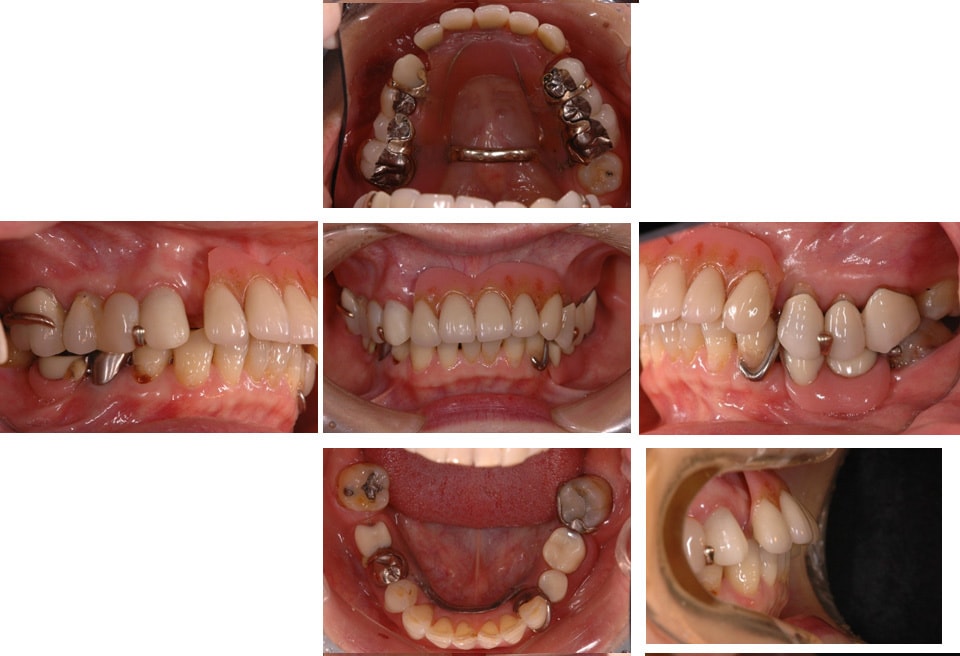

かみ合わせが崩れてしまった場合

治療前のかみ合わせのままで治療しても長持ちしないこと、本来のかみ合わせから崩れてしまっていると判断し、お口の中を総合的に治療する治療方法を提案させていただき治療を行いました。

治療前

治療後

咬むと前歯が痛いと来院された患者さん。奥歯がないため、前歯に負担がかかり、下の歯がないまま放置していたため、上の歯が下に下がってしまうなど様々な問題をお口の中に抱えていました。

残すことが出来ない歯の抜歯などを行うと、すれ違い咬合という治療するには難しいかみ合わせであったことなど、仮の入れ歯などで咬合状態の経過観察などを行ったため治療期間は約2年ほどかかりました。

治療の内容にもよりますが、しっかり診断し治療を行っていくとどうしても治療期間がかかってしまいます。患者さんにはその点ご理解いただけると幸いです。